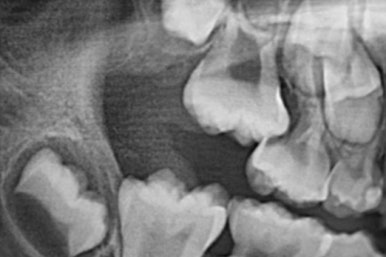

만약 저 상태로 방치한다면 어금니에 걸려있는 유치가 조기에 발치되어 더 큰 문제가 생깁니다.

이 X-ray는 다른 어린이의 사진인데, 위와 같은 경우를 방치했을 때 유치가 제 시기보다 조기에 빠지게 되고 그러면 어금니가 앞쪽으로 쏠려서 나고, 해당 부위의 영구치가 나올 자리를 아예 없애버립니다. 문제가 복잡해 지지요.